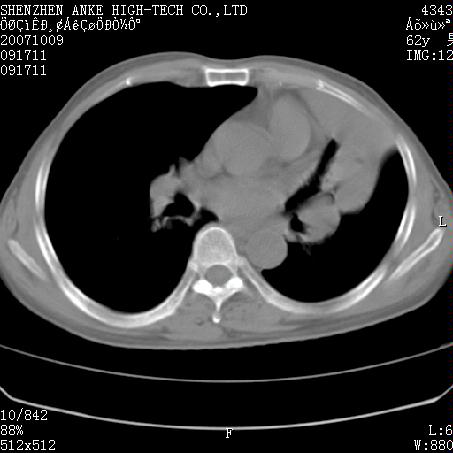

患者:男,62岁,咳嗽、胸痛、咯血约2月

左侧中央型肺癌伴上叶肺不张\\阻塞性肺炎.

左侧中央型肺癌伴上叶肺不张、阻塞性肺炎、纵隔淋巴结转移。支持!

左侧中央型肺癌伴上叶肺不张及阻塞性肺炎,纵隔内淋巴结转移